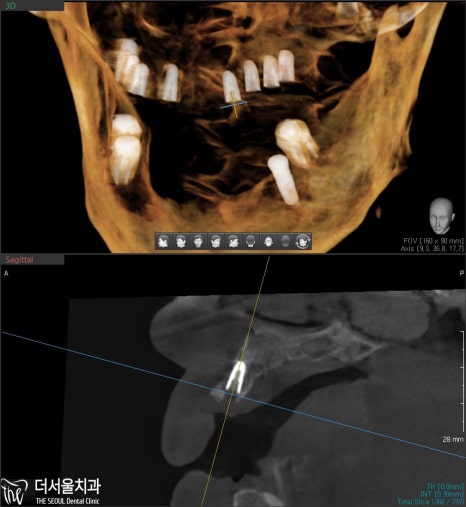

그리고 한달 뒤,

아래 부분도 마찬가지로

임플란트 수술이 이뤄졌습니다.

식립하고 엑스레이와 CT를 찍어봤는데,

좋은 결과가 나왔네요. ^^